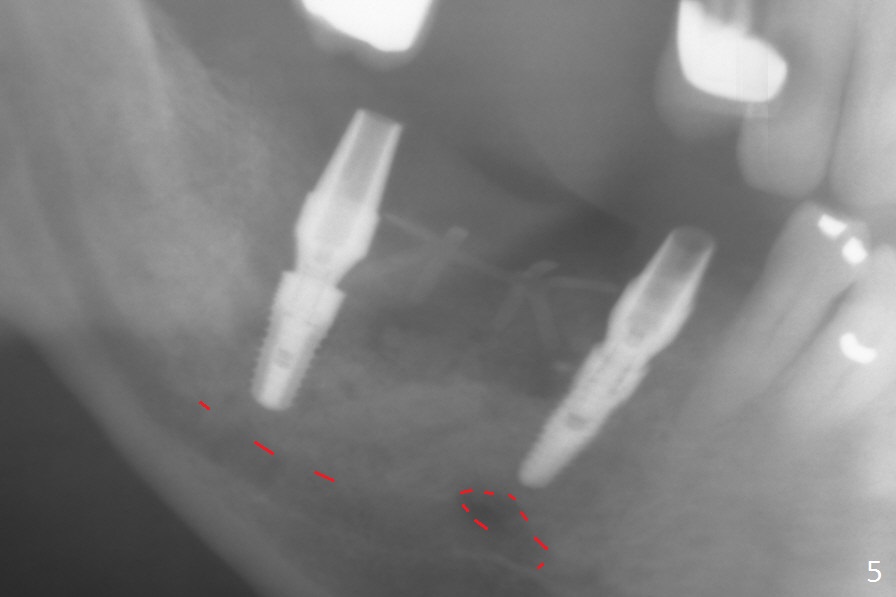

Initial osteotomy at #29-30 shows that there is clearance at #31, but not at #30 (Fig.1 (red dashed line: the superior border of the Inferior Alveolar Canal)) and that the osteotomy at #29 is close to the root of #28 (Fig.2). Moving the osteotomy of #29 distally using Lindamann bur is not sufficient (Fig.4 when a 3.8x10 mm drill is in place). A de novo osteotomy is established distally (Fig.5,6 (red dashed line: old osteotomy)).

At #31, the implant has to be placed low because of low buccal bone (Fig.8 B (vs. much higher lingual (L) one) in spite of 2 mm implant being coronal to the distal bone (Fig.3 ^). The margin of the abutment with 6 mm cuff appears apical to the distal crest (Fig.3 *). Bone graft is placed around the exposed implant threads (Fig.6 *) after placement of Osteogen plug between the implants (P). After placing PRF membrane (Fig.7 M) and plug (P) over the bone graft, Cytoplast (Fig.6,8 C: non-resorbable membrane) is used to assist wound closure. Finally periodontal dressing is applied for further wound protection (Fig.9).